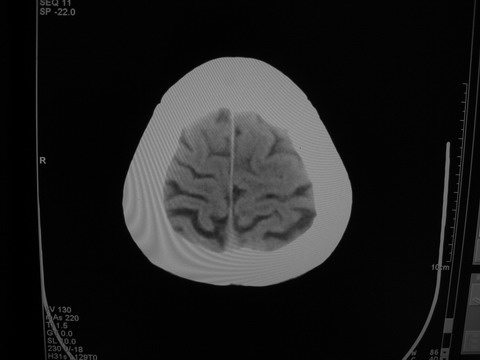

患者 男 69岁 头晕头痛不适

多发病灶,指状水肿,首先诊断转移瘤。

多个结节并周围大面积水肿区,多考虑多发性脑转移瘤

小病灶、大水肿,病灶多发,首先考虑多发转移瘤;建议查原发灶。

额顶叶多发小病灶、大水肿,首先考虑多发转移瘤;建议查原发灶

脑内多发病灶,小病灶,大水肿。

典型转移性肿瘤。

应进一步检查,查找原发病灶。

结果 : 该患者结肠癌病史5年 考虑脑转移